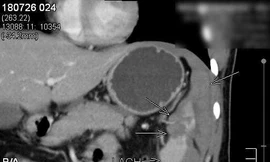

Từ khóa: "vỡ lá lách"

5 kết quả